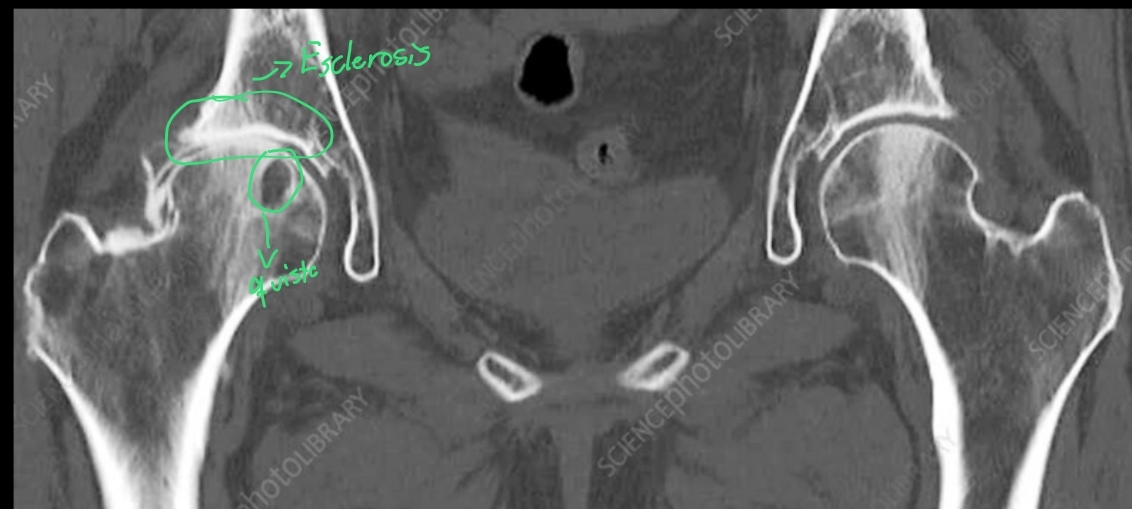

Q

En la TC se pueden apreciar los mismos datos de una coxartrosis que en una Rx?

Verdadero

- Osteofitos

- Disminución del espacio articular

- Esclerosis osea

- Quistes subcondrales

- deformidad osea